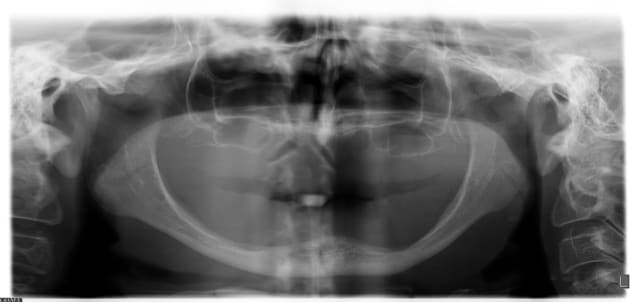

Femme, bonne santée, 58 ans.

Perte osseuse, disons, avancée.

On lui propose un all-on-4 avec MCI, vient pour un 2e avis.

Suggestions ?

C'est un patiente qui porte certainement déjà deux complets, je ne vois pas l'intérêt de la MCI, sinon "marketing"...

edit: d'ailleurs on les voit à la pano les complets ^^

Déjà avec deux implants symphysaires et des Locator, ça lui changerait la vie, car vu la résorption, le complet du bas doit bien se balader. Après, faut voir ses attentes.

Pour le bas, il ne semble par rester grand chose pour proposer du fixe.